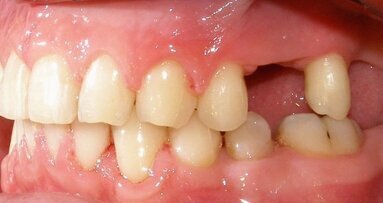

Dva dana ranije, u saobraćajnoj nezgodi, malu Marlenu udario je automobil. Na desnom gornjem centralnom sekutiću bila je prisutna fraktura gleđi i ...